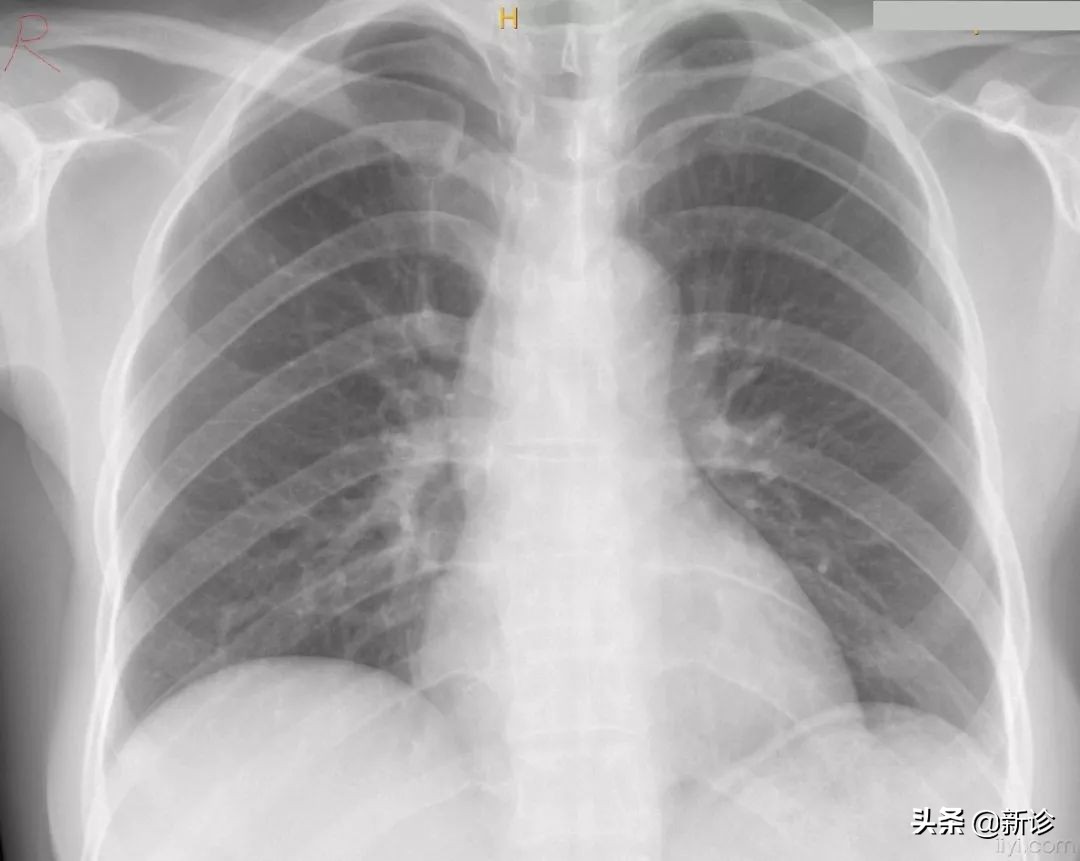

事实上,如果在孕期拍一次X胸片,不能作为流产的指征。

美国妇产科协会(ACOG)在2017年发布了指南,明确指出:只要涉嫌剂量不超过50mSV,就不会对胎儿产生损伤。

那50mSV又是个什么概念的,大概相当于你做6次胸部CT,25次脑部CT,2500次胸片,5000次牙片......

所以偶尔一次胸片或是CT,其实并不会对胎儿产生什么不利影响。